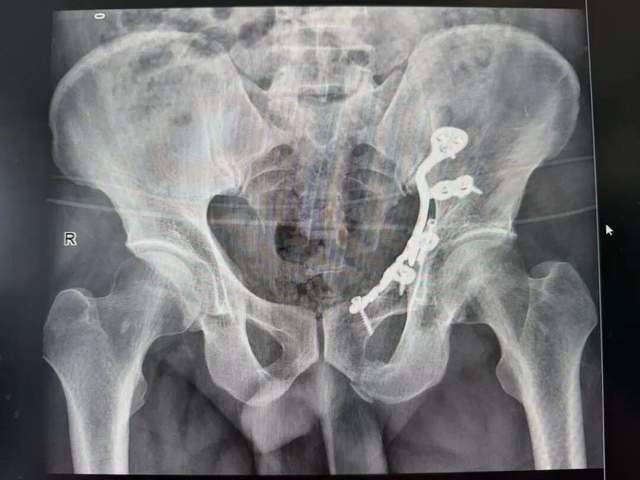

近日,46岁的王先生(化名)不慎从高处坠落,左髋部剧烈疼痛,活动严重受限,被紧急送至我院急诊科。急诊科立即启动创伤救治绿色通道,争分夺秒完成全身重点部位影像学检查。检查结果显示:患者左侧耻骨上、下支及髂骨骨折,同时伴有L1左侧横突骨折——这是一种典型的高能量损伤导致的复杂性骨盆骨折。

面对严峻挑战,骨科主任尹绍猛立即组织多学科会诊。经过周密准备,尹绍猛亲自主刀,带领骨科团队为患者施行了"骨盆骨折切开复位内固定术+植骨术"。手术团队首先在C型臂X光机精准导航下,细致显露骨折部位,巧妙避开重要血管神经,将粉碎的骨折块逐一精确复位,重建了骨盆环的完整性。随后采用先进的内固定系统进行牢固固定,并在骨缺损处植入人工骨材料,为骨愈合创造了良好条件。